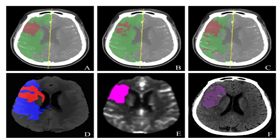

已应用于西医医疗设备医疗诊断和中医诊断,,,为诊疗提供辅助决策支持。。。